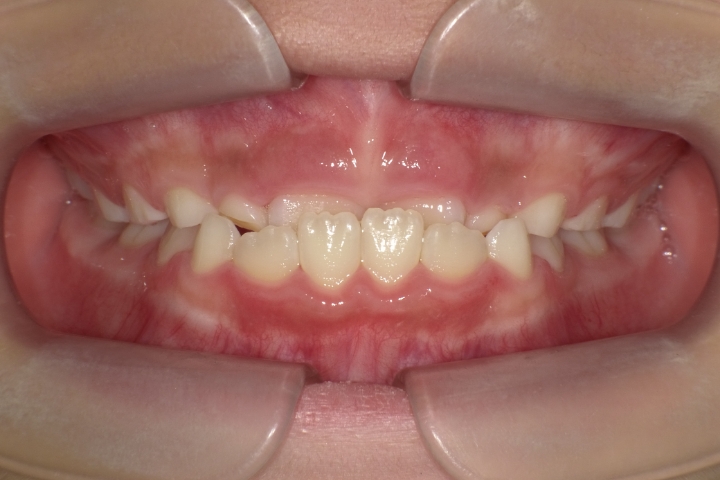

きれいな歯並びは健康的で若々しく、お顔の印象が変わります。

当医院では、歯並びに対する各種治療を行っております。

また、ワイヤー矯正やインビザライン矯正(マウスピース矯正)等、症例に合わせて行っております。

お子様においては、プレオルソ治療も行っております。受け口や出っ歯等、早期に解決すべき歯並びに対して、高いコストパフォーマンスを上げております。